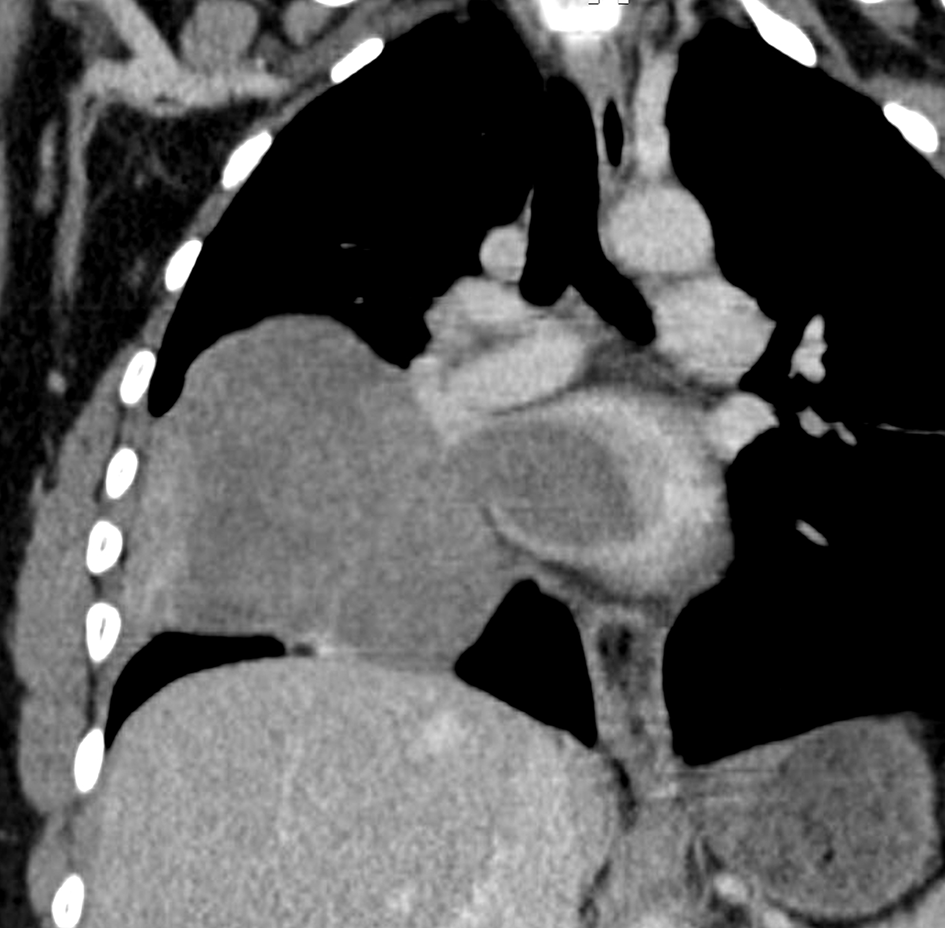

A second huge mass compressed the right atrium posterior wall. Following respiratory stabilization, transesophageal echocardiography confirmed TTE results and revealed an extended mass into LA via the right inferior pulmonary vein (RIPV) (Figure 2). Cardiac computed tomography (CT) revealed a large (100 × 70 × 100) mediastino-pulmonary mass extending to LA via RIPV (Figure 3).

PTs or cystosarcoma is a rare breast neoplasm.1 These types of tumors are commonly manifested in the breast tissue and are usually benign; however, they might rarely be malignant.2,3 A malignant tumor has a potential to metastasize to distant organs, such as lung, bone, and liver.8 Our case revealed concomitant pulmonary and cardiac metastases, which is unusual, and it is associated with poor prognosis. It has been reported that cardiac invasion could be caused by hematogenous spread, direct extension, or via the lymphatic route.9 In the case of this patient, direct extension from pulmonary metastasis to RIPV is the probable route of metastasis. Reported cases of cardiac metastasis are mostly located in the right heart with the possibility of right ventricle outflow tract obstruction.10 To the best of our knowledge, this is the first case of LA location, complicated by severe mitral obstruction and acute heart failure. The clinical expression of cardiac metastasis is mainly dependent on the tumor burden and location.6 As in the case of our patient, cardiac metastasis can manifest with dyspnea and chest pain, or it can be asymptomatic. Previously, malignant cardiac metastasis had poor prognosis and very rare cases were identified at autopsy.11 However, advances in imaging tools such as echocardiography allows for detection and confirmation of intra-cardiac mass and eventual valve or cavity obstruction. However, echocardiography is limited in the differentiation between PTs, myxoma, fibroadenoma, and thrombus.11 In our case, echocardiography revealed severe mitral obstruction by an intra-LA mass. Cardiac CT and MRI provide multiple views in different axes with a precision of limits as well as intra, and extra cardiac extension, thus allowing a better distinction between the thrombus and other masses.12 The results of the echocardiography, cardiac CT, and MRI for our patient confirmed the intra and extra cardiac location of the tumor and its LA access from RIPV to the mitral valve. Therapeutic approaches, including chemotherapy, radiotherapy, and hormonal therapy are still controversial.7 The surgical excision of cardiac metastasis from a malignant PTs was described in few reports.13 This type of intervention could be an urgent life-saving therapeutic strategy in case of right ventricle outflow obstruction or mitral obstruction, and it can also improve the patient’s quality of life in the short term, as it was in our case.14,15 However, intra-operative mass manipulation could cause tumor dissemination, thus leading to a risk of further metastasis development.11,16 This may explain the hudge relapse of mediastinal mass with tracheal invasion in our patient. In this case report the major limitations were the delay in diagnosing cardiac and pulmonary metastases and the lack of immunohistochemical analysis of the tumor.